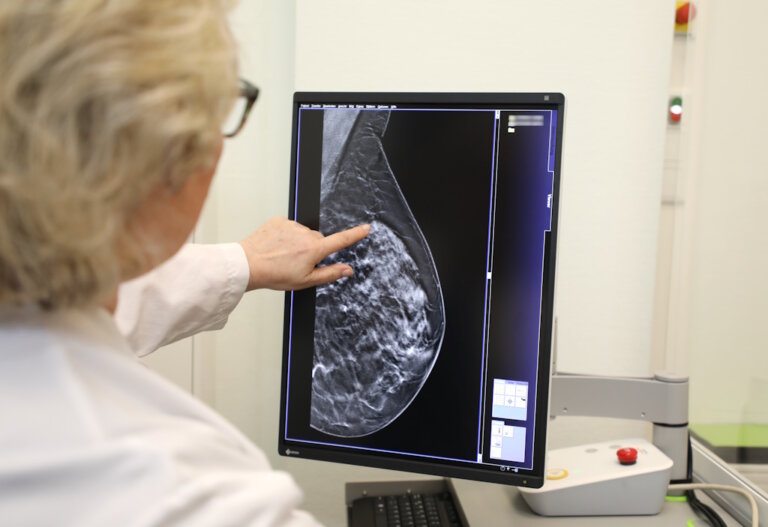

Mammographie Tut Das Weh. Digital mammography at the Radiologie München Dieses Zusammendrücken kann unangenehm, manchmal auch schmerzhaft sein Warum tut Mammographie weh? Um das Brustgewebe gut darstellen zu können, wird die Brust kurz zusammengedrückt

Digital mammography at the Radiologie München from www.radiologie-muenchen.de

Digital mammography at the Radiologie München